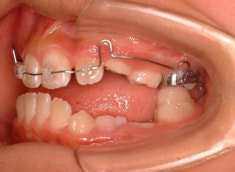

治療法:上顎拡大装置+フルパッシブブラケット(クリアスナップ)+フェイスマスク等

治療後(12ヶ月後)

治療開始から約3ヶ月後

外科矯正も回避できて、さらに非抜歯で本格矯正を行うことができると診断し、現在2期治療中です。

少し大臼歯の傾斜が認められます。

上顎8番は先天欠如、下顎8番は埋伏しております。